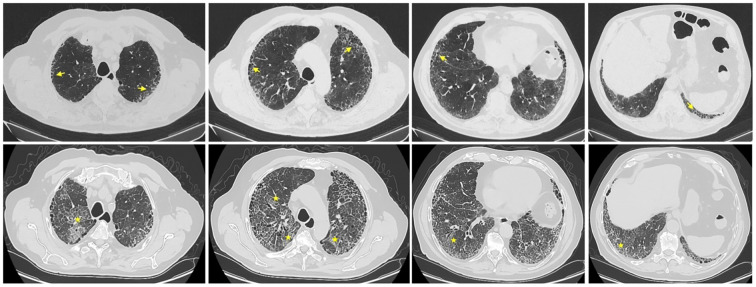

Abstract Image